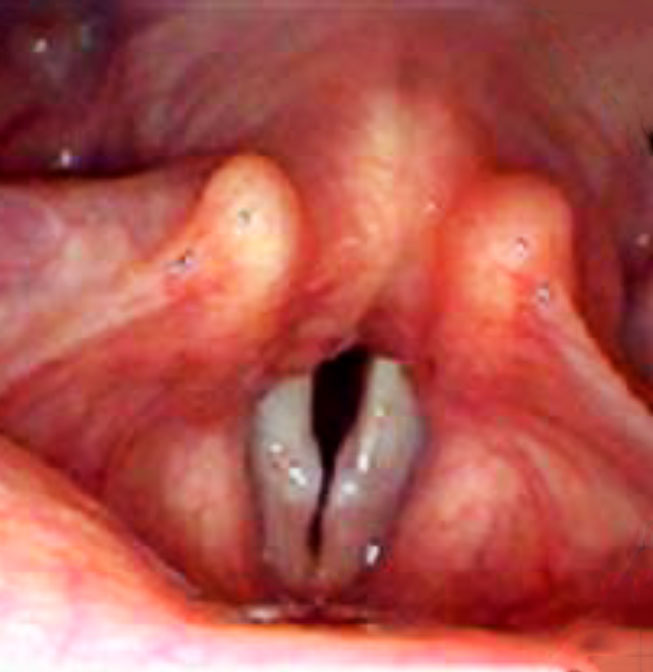

- Nódulos. Formaciones de pequeño tamaño que asientan en el territorio de las cuerdas vocales, produciendo dificultades en el cierre de estas y generando una alteración de la calidad de la voz (disfonías). Generalmente, se producen como consecuencia de un sobre esfuerzo de la voz tanto en niños como en adultos.

- Pólipos. Formaciones de pequeño o mediano calibre de naturaleza benigna que pueden localizarse en la extensión de las cuerdas vocales, generalmente con carácter unilateral, que dificultan el cierre normal de las mismas, dando lugar a una alteración tanto de la calidad como de la cantidad de voz.

- Inflamaciones de las Cuerdas Vocales. Procesos motivados por el mal uso de la voz, abuso de tabaco y/o alcohol, infecciones bacterianas o virales. (papilomatosis laríngea), así como por influencias medioambientales (humo, inhalaciones de gases, etc.).

- Disfonías. Se caracterizan por una pérdida de la calidad de la voz, como consecuencia de procesos inflamatorios o tumorales que asientan en las estructuras de la laringe.

- Afonías. Es la perdida total de la voz causada por infecciones bacterianas o virales, que generan una inflamación importante de las mismas; tumoraciones benignas o malignas laríngeas y manifestaciones neurológicas en la inervación de las cuerdas vocales, secundarias a enfermedades degenerativas o traumatismos sobre los nervios laríngeos (traumatismos laríngeos, cirugía cervical y tiroidea).